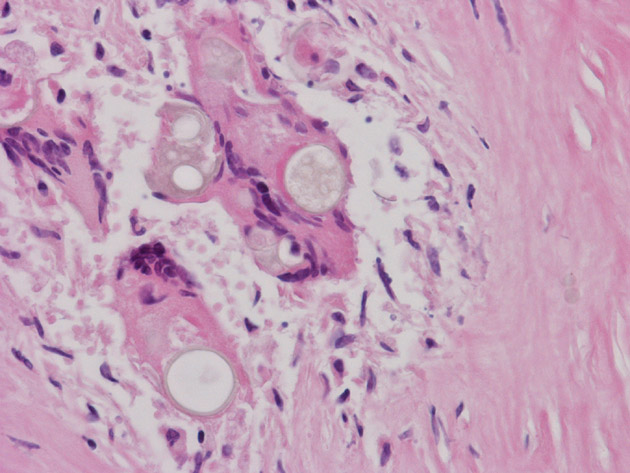

Hematoxylin & eosin

High magnification HE stain image: Note that the fungal organisms do not take up the stain and remains either as a pale, round clear structure or with some bluish content.

• In Slide #1, the salient pathologic change here is a necrotizing granulomatous inflammation of the leptomeninges associated with foreign body type giant cells and round inclusions that are morphologically consistent with Coccidiodes species. These organisms can be well demonstrated by PAS stain (see below). Note that there is fibrotic thickening of the leptomeninges (outlined by the arrows). The granulomas are only accompanied by a small amount of lymphocyrtes. Note that the granulomas are limited to the meninges.

• The spheres of Coccidioides are among the largest that are seen in histologic sections and range from 30 to 60 μm. Most of the fungal organisms are likely to be non-viable in this case because of aggressive fungal therapy. The impressive foreign body type giant cell reaction is likely a reaction to the non-viable spores.